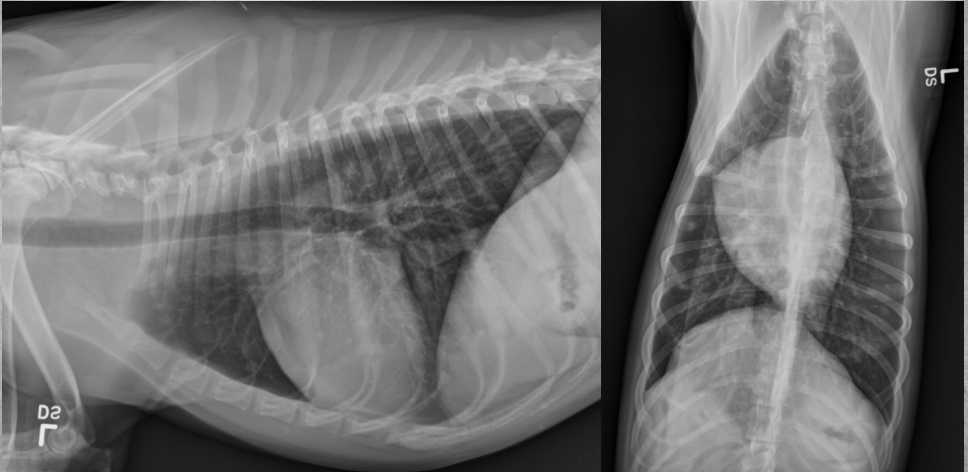

● 12 yo dog

● Coughing for 2 months

alveolar pattern caudodorsally (black tree visible)

fat in ventral thorax

cardiac silhouette lifted and rounded, maybe free fluid

on VD: mass effect